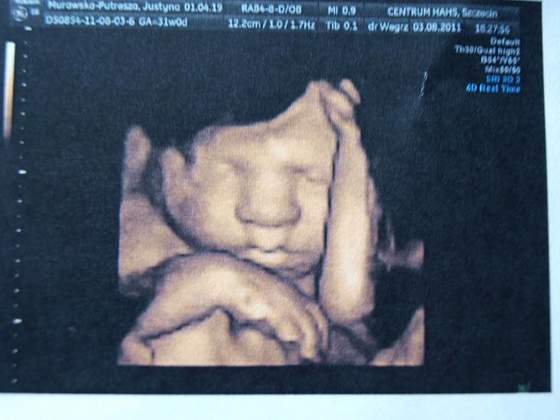

Ja po usg 30tyg na którym byłam równo w 31 tyg :)

A więc synuś pozostał synusiem, pięknie jajeczka mamusi pokazał :)

Waga 1678g wszystko jest w porządku, zdrowiutki to najważniejsze :)))

piekny chlopczyk, piekny :))))))))))

Super fotki. Jakie wyraźne. :tak:

justyś ale piękny chłopczyk, jak się fajnie mizia po buzi :))))